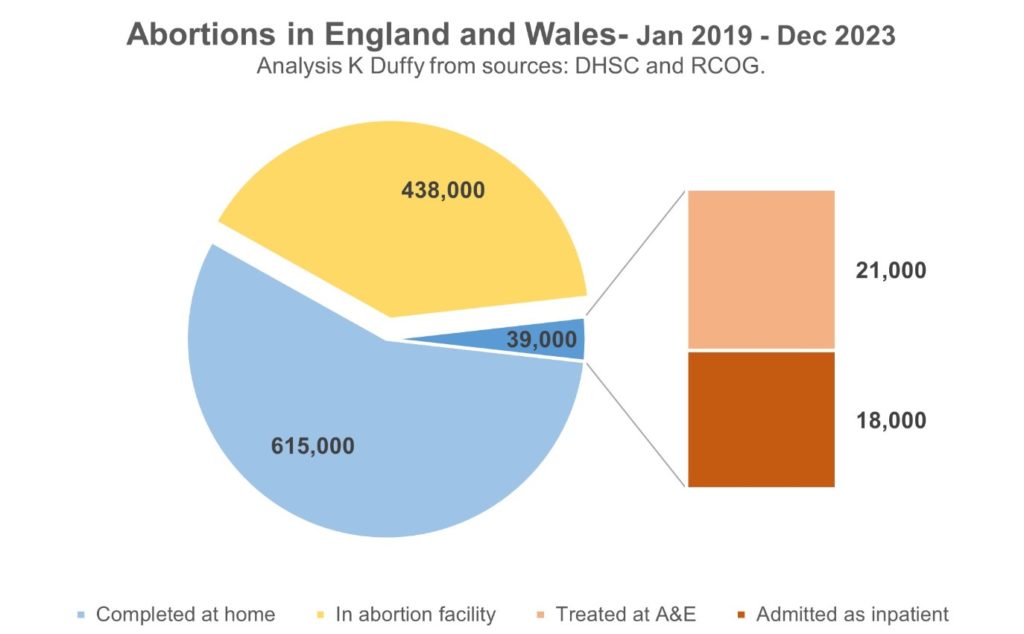

Aumentan hospitalizaciones de mujeres por abortos caseros en Inglaterra y Gales

Reino Unido.— Resultados de un estudio liderado por el consultor de salud independiente Kevin Duffy arrojaron una tendencia preocupante en el sistema de salud del Reino Unido.

El estudio revela que en los últimos cinco años, al menos 39 mil mujeres en Inglaterra y Gales han sido tratadas en hospitales del Servicio Nacional de Salud (NHS) debido a complicaciones derivadas de abortos caseros con medicamentos fallidos o incompletos.

En diciembre de 2018, el Secretario de Estado de Salud y Asistencia Social permitió a las mujeres autoadministrarse la segunda parte de un aborto con medicamentos en casa, y esta medida se amplió a ambas partes del proceso en marzo de 2020 como respuesta a los confinamientos por la pandemia de Covid-19.

El Real Colegio de Obstetras y Ginecólogos (RCOG) advierte que 1% de todos los casos de aborto con medicamentos fracasan, mientras que hasta el 6% pueden ser incompletos, lo que requiere atención médica adicional. Sin embargo, los proveedores de servicios de aborto y el Departamento de Salud y Asistencia Social han subestimado estas complicaciones, según el informe reciente.

El análisis de datos revela que el 2.8% de las mujeres que autogestionaron sus abortos con medicamentos en casa fueron admitidas posteriormente en hospitales para recibir tratamiento quirúrgico, lo que sugiere una tasa total de complicaciones del 6%. Estas cifras, consistentes con investigaciones independientes, plantean serias preocupaciones sobre la seguridad y el apoyo a las mujeres que optan por el aborto con medicamentos en el hogar.

El aumento de abortos registrados en el primer semestre de 2022, con un incremento del 17% en comparación con el mismo período de 2021, es un indicador adicional de la magnitud del problema. Organizaciones independientes han expresado su preocupación por el impacto emocional y físico en las mujeres, así como por la falta de apoyo adecuado en este proceso.